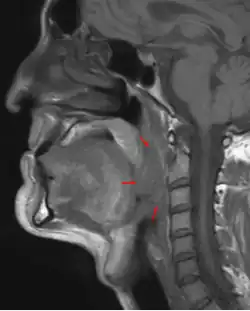

Oropharyngeal cancer (from right tonsil, HPV-negative), T4a N2c, 48-year-old man.

Diagnosis is by biopsy of observed abnormal tissue in the oropharynx.